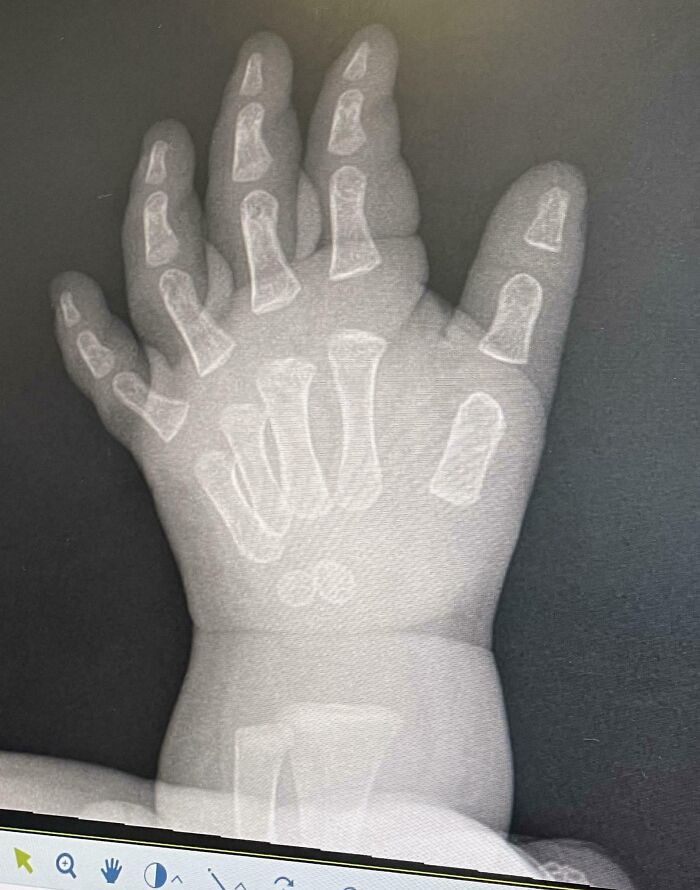

#6 Did You Know: An X-Ray Of A Baby’s Hand Makes It Look Like Their Bones Are Just Kinda Floating Around In There

Our 11-month-old somehow hurt her hand/wrist, and in trying to figure out what was wrong we got some x-rays. Unfortunately nothing conclusive came from the scans, but I thought the x ray itself was mildly interesting. Baby girl is going to be fine, apparently infants have Wolverine-like regenerative powers.